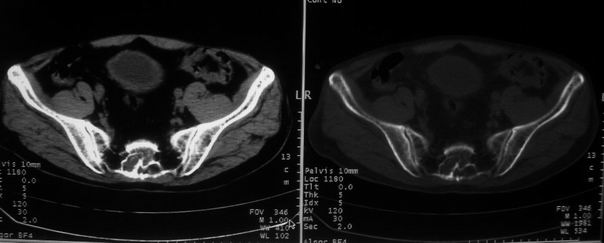

男,85岁,排尿困难。骶椎有问题吗?

1)考虑前列腺增生症并阻塞性膀胱炎。2)骶椎右侧类似囊状骨质密度减低区,边缘骨质硬化,其内为软组织密度影填塞,相邻之骶椎椎管受压变形;考虑为骶椎右侧囊肿或神经纤维瘤。

建议:行mri检查。

骶椎脊索瘤

1)前列腺明显增大,突入膀胱,各叶比例协调,密度均匀,精囊腺及精囊角正常;考虑前列腺增生症并阻塞性膀胱炎。2)骶椎右侧类似囊状骨质密度减低区,边缘骨质硬化,其内为软组织密度影填塞,相邻之骶椎椎管受压变形;考虑为骶椎右侧囊肿或神经纤维瘤。